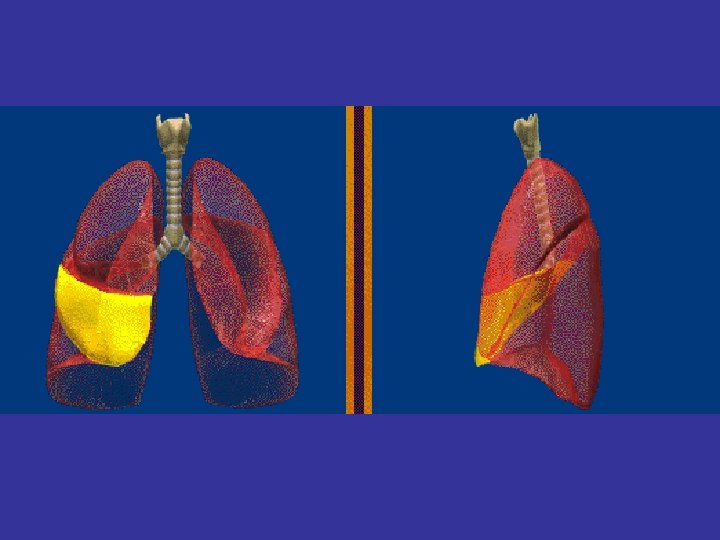

Lobes and Fissures

A A This patient has a pleural effusion extending into the fissure. B